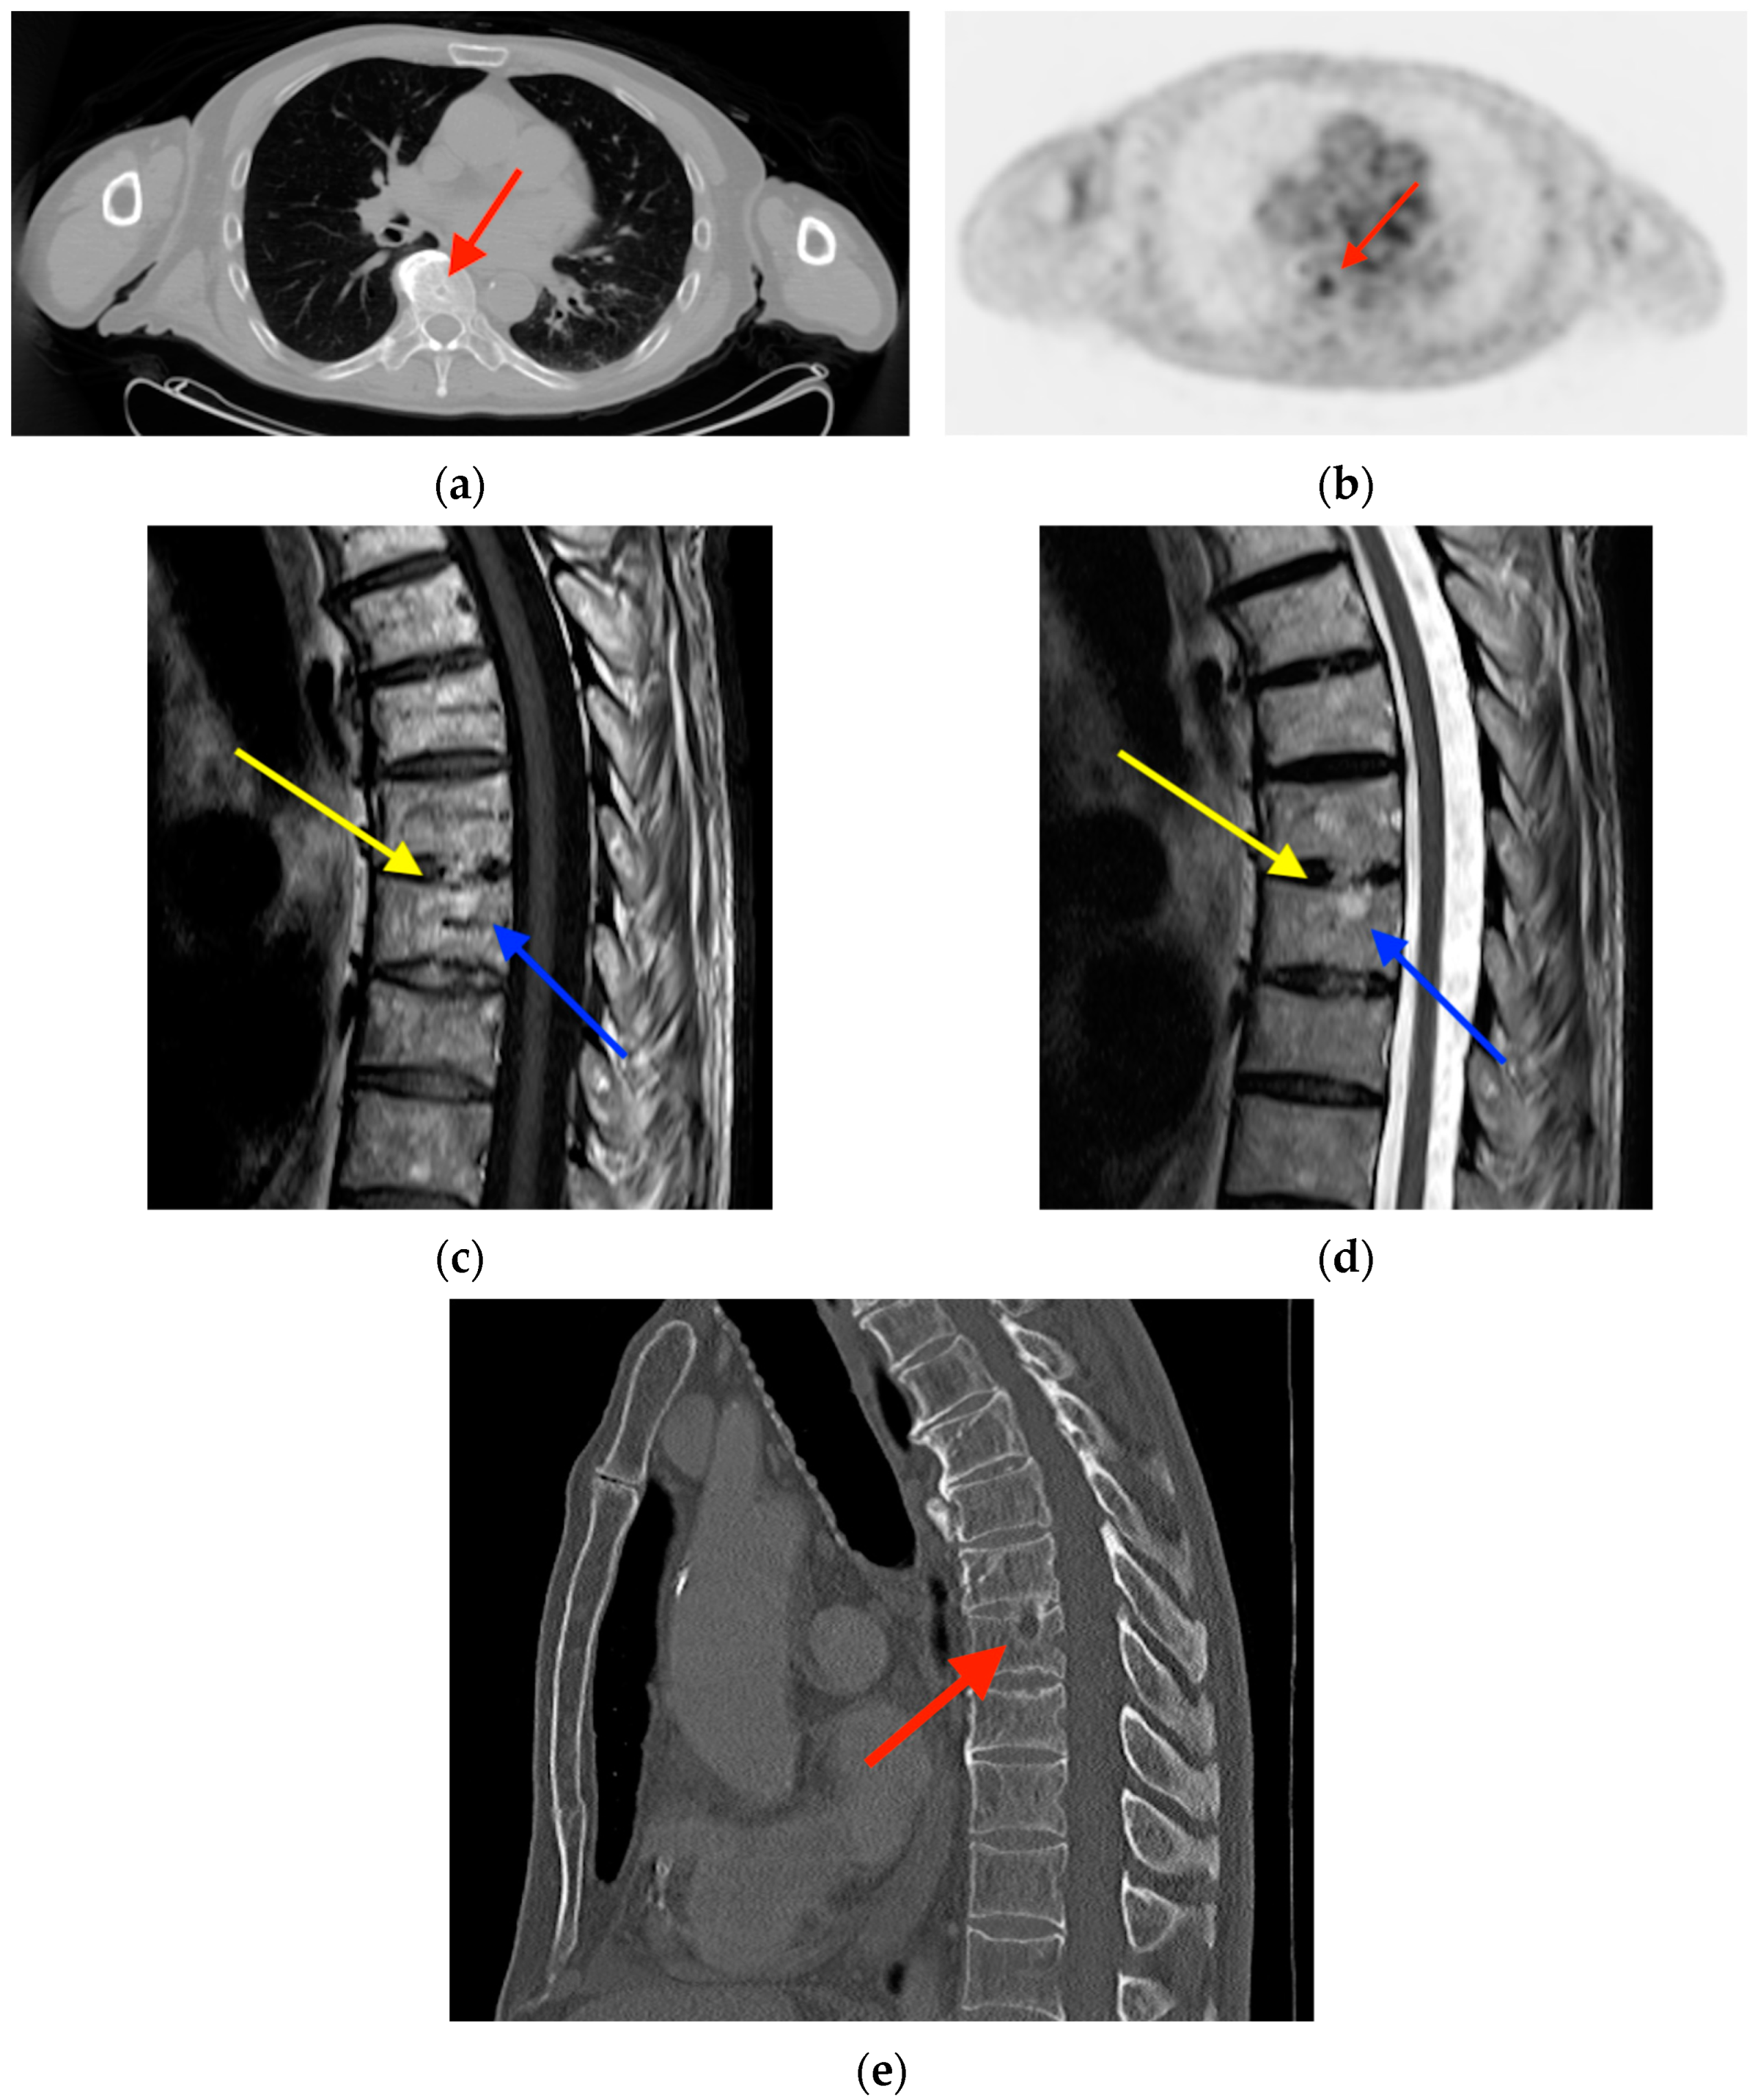

2.5. Vertebral Hemangioma

- Pastushyn, A.I.; Slin, E.I.; Mirzoyeva, G.M. Vertebral hemangiomas: Diagnosis, management, natural history and clinicopathological correlates in 86 patients. Surg. Neurol. 1998, 50, 535–547. [Google Scholar] [CrossRef] [PubMed]

- Gaudino, S.; Martucci, M.; Colantonio, R.; Lozupone, E.; Visconti, E.; Leone, A.; Colosimo, C. A systematic approach to vertebral hemangioma. Skelet. Radiol. 2015, 44, 25–36. [Google Scholar] [CrossRef] [PubMed]

- Kim, C.H.; Kim, S.W. Rapidly Progressive Atypical Vertebral Hemangioma: A Case Report. Korean J. Neurotrauma 2020, 16, 320–325. [Google Scholar] [CrossRef] [PubMed]

- Gerard, P.S.; Wilck, E. Spinal hemangioma. An unusual photopenic presentation on bone scan. Spine 1992, 17, 607–610. [Google Scholar] [CrossRef]

- Domínguez, M.L.; Rayo, J.I.; Serrano, J.; Sánchez, R.; Infante, J.R.; García, L.; Durán, C. Vertebral hemangioma: Cold vertebrae on bone scintigraphy and fluordeoxy-glucose positron emission tomography-computed tomography. Indian J. Nucl. Med. 2011, 26, 49–51. [Google Scholar] [CrossRef]

- Solav, S.V.; Savale, S.V.; Patil, A.M. False-positive FDG PET CT Scan in Vertebral Hemangioma. Asia Ocean. J. Nucl. Med. Biol. 2019, 7, 95–98. [Google Scholar] [CrossRef]